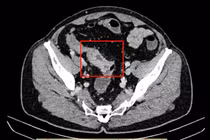

Kết quả chụp X-quang, siêu âm và cắt lớp cho thấy dạ dày chứa nhiều chất đặc quánh, hình ảnh bã thức ăn gây tắc ruột. Người bệnh được chẩn đoán tắc ruột do bã thức ăn, chỉ định phẫu thuật mở dạ dày lấy khối bã. Sau mổ, bác sĩ ghi nhận khối bã lớn, cứng, màu nâu đen, nguyên nhân gây tắc nghẽn kéo dài dẫn đến nhiễm trùng, suy thận cấp và suy đa tạng.